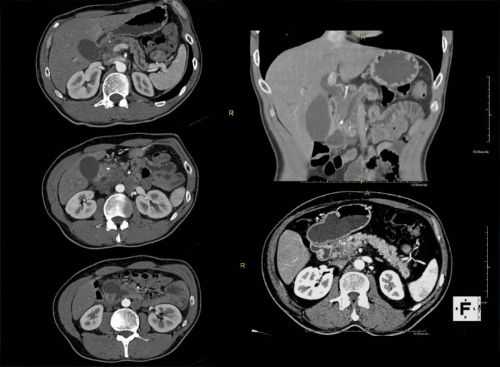

Что показывает МРТ поджелудочной железы? Особенности метода позволяют получить информацию о состоянии не только ткани органа, но также его протоков. Нередко томография дает возможность оценить состояние желудка и печени. По результатам исследования врач может определить наличие камней в протоках, новообразования в тканях.

Результаты могут отличаться в зависимости от того, где сделано исследование. Современные аппараты для магнитно-резонансной томографии позволяют добиться точности в 97% и более. Особенно важна оценка состояния тканей хвоста и тела железы, так как в них наиболее часто могут развиваться карциномы – опасные злокачественные новообразования. При помощи этого метода исследования можно выявить опухоли диаметром менее двух сантиметров.

Описание МРТ обычно включает в себя:

- размеры патологического очага – определяются по трем осям, измеряются в миллиметрах или сантиметрах,

- форма – если новообразование имеет правильные очертания, скорее всего, это доброкачественный процесс,

- контуры – этот параметр также используется для выяснения доброкачественности опухоли. Злокачественные новообразования имеют неровные контуры, а доброкачественные, наоборот, отличаются четкими границами,

- интенсивность – чем более яркое изображение, тем выше плотность ткани. Таким образом отличают кисты от опухолей,

- отношение к расположенным рядом тканям – злокачественные образования легко прорастают в близкие органы. Также оценивается состояние естественных полостей рядом с железой – врач определяет наличие в них жидкости, которая может быть гноем или кровью. Это обычно используется при диагностике панкреатита.

МРТ поджелудочной железы даёт возможность детально визуализировать контуры и структуру паренхимы поджелудочной железы – выявлять участки диффузных изменений, инфильтрации. Небольшие очаговые образования (включая кистозные и солидные опухоли) размерами от 5–10 мм.

Компьютерная томография при патологии поджелудочной железы используется чаще, чем МРТ. Данный метод особенно хорош при травмах, потому как при КТ позволяет лучше оценивать травму костей и влияние этой травмы на орган.